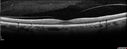

64 year old female: She woke up with a blurry area in the vision of the left eye. She was concerned (she has been in the optical business for 36 years). Her ophthalmologist asked her to come back for a visual field and then she had trouble finding someone on her insurance. Diagnosed at age 10 with RA (juvenille idiopathic). She is now doing a little better. She is now weaning off the prednisone very slowly (now on 3 mg per day). She has no eye pain and no pain on eye motion. She does have headaches which are the same as her usual headaches. 3-4 days prior to the vision loss in the left eye she did have an intermittent fever and upset stomach. She was helping with her sons cats a few months ago. She also felt neck pain and swollen lymph nodes around the back of her neck. VA OD: Dcc20/20 NccJ1 VA OS: Dcc20/160 NccJ16-1 Bartonellas IgG was very positive - IgM negative (this is true about 50 percent of cases) Her vision returned to 20/25 within about 2 months

Neuroretinitis and Multifocal Retinitis424 views62 year old female with vision loss in the left eye to 20/160. Positive Bartonellas IgG. Vision recovered in 2 months. She was treated with Oral Erythromycin BID for 2 weeks.00000